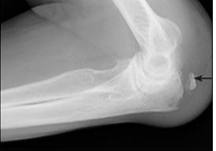

Mecanismo de lesion de esta fractura

Mecanismo INDIRECTO

Caida sobre la mano extendida con el codo en flexion

Se produce por avulsion de una parte de la apofisis por una contraccion del triceps

Mecanismo DIRECTO

Golpe directo al codo por caida o trauma